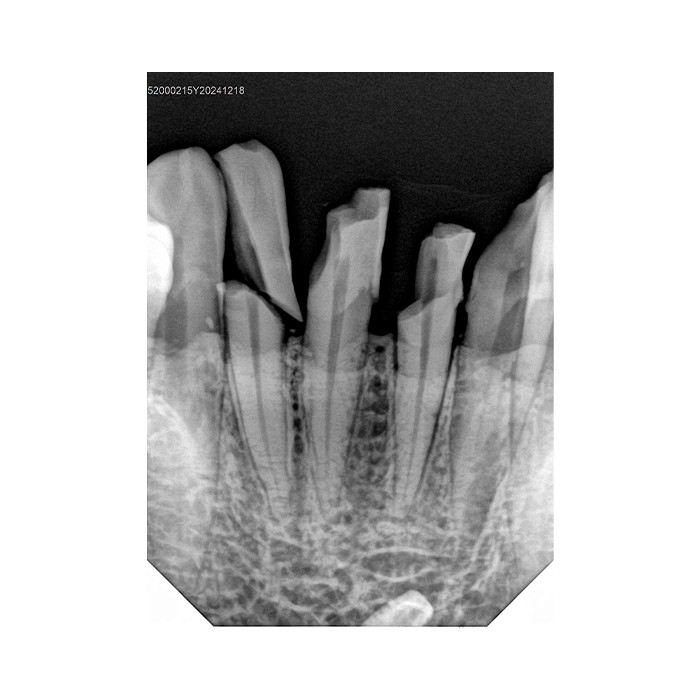

В современной стоматологии точность и скорость диагностики являются ключевыми факторами успешного лечения. Цифровой радиовизиограф Handy HDR-380 — это профессиональное решение, созданное для того, чтобы вы могли получать детальные рентгеновские снимки зубов мгновенно, минимизируя лучевую нагрузку на пациента и экономя ваше время. Этот аппарат сочетает в себе надежность, простоту использования и высокое качество изображения, необходимое для постановки точного диагноза.

- Высокое разрешение и детализация. Датчик обеспечивает четкое, контрастное изображение, позволяющее визуализировать мельчайшие детали: начальный кариес, состояние корневых каналов, периапикальные изменения, что напрямую влияет на качество диагностики.

Области применения

Handy HDR-380 незаменим для широкого спектра диагностических задач в терапевтической, хирургической, ортопедической и ортодонтической стоматологии. С его помощью вы сможете выполнять прицельные внутриротовые снимки для оценки состояния отдельных зубов, пародонта, контроля качества пломбирования каналов и установки имплантатов.